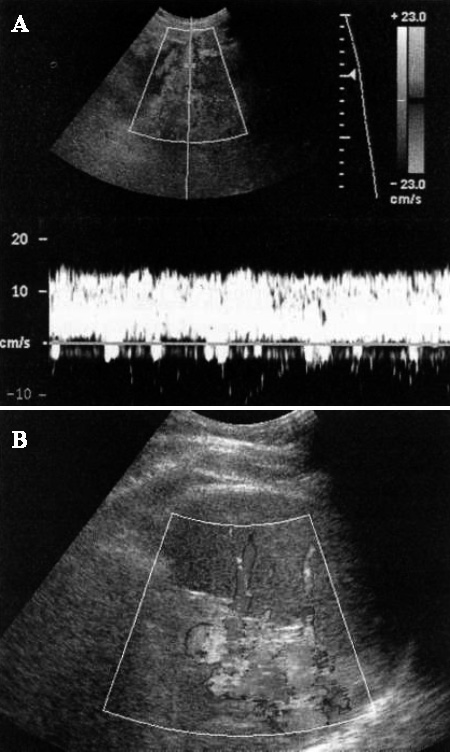

При острой или подострой портальной гипертензии из-за повышения давления увеличивается диаметр воротной вены, в результате чего снижается средний показатель скорости кровотока и формируется монотонный кровоток (без дыхательных колебаний). По мере дальнейшего повышения давления кровоток может стать двухфазным («туда-сюда») и даже обратным (фото 4).

Допплерография: Портальная гипертензия

Фото 4. Портальная гипертензия. А – цветовая допплерограмма демонстрирует венозный поток: стрелкой обозначен гепатофугальный кровоток, направленный от печени. В – спектральная допплерограмма правой воротной вены подтверждает гепатофугальный кровоток